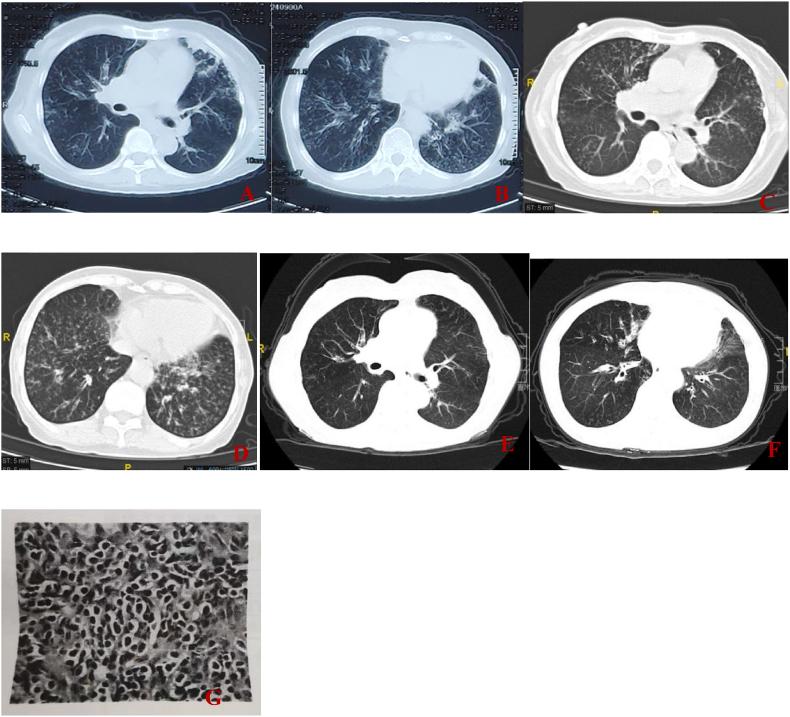

Thymoma with Immunodeficiency (Good's Syndrome, GS) is a rare association between thymoma and immunodeficiency, first described over 60 years ago. Patients with GS typically present with thymomas, reduced or absent B cells in the peripheral blood, hypogammaglobulinemia, and defects in cell-mediated immunity. We report the case of a 67-year-old woman diagnosed with GS following the development of a progressive, severe, refractory pulmonary infection and diffuse panbronchiolitis (DPB). She also had diabetes, characterized by anti-glutamic acid decarboxylase antibody positivity, leading to a diagnosis of latent autoimmune diabetes in adults (LADA). A thorough review of existing literature revealed that GS is often confirmed after multiple episodes of opportunistic infections or autoimmune diseases post-thymoma surgery. Due to their immunodeficiency, GS patients frequently suffer from recurrent infections over extended periods, and some succumb to severe infections. Regular immunoglobulin infusions may be effective in treating GS.

胸腺瘤伴免疫缺陷(古德综合征,GS)是胸腺瘤与免疫缺陷之间的一种罕见关联,60多年前首次被描述。GS患者通常表现为胸腺瘤、外周血B细胞减少或缺失、低丙种球蛋白血症以及细胞介导免疫缺陷。我们报告了一例67岁女性病例,该患者在发生进行性、严重、难治性肺部感染和弥漫性泛细支气管炎(DPB)后被诊断为GS。她还患有糖尿病,其特征为抗谷氨酸脱羧酶抗体阳性,导致诊断为成人隐匿性自身免疫性糖尿病(LADA)。对现有文献的全面回顾显示,GS通常在胸腺瘤手术后多次发生机会性感染或自身免疫性疾病后得到确诊。由于免疫缺陷,GS患者经常在很长一段时间内反复感染,一些患者死于严重感染。定期输注免疫球蛋白可能对治疗GS有效。